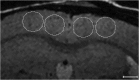

The ability to detect individual Alzheimer's amyloid plaques in vivo by magnetic resonance microimaging (MRI) should improve diagnosis and also accelerate discovery of effective therapeutic agents for Alzheimer's disease (AD). Here, we perform in vivo and ex vivo MRI on double transgenic AD mice as well as wild-type mice at varying ages and correlate these with thioflavin-S and iron staining histology. Quantitative counts of individual plaques on MRI increase with age and correlate with histologically determined plaque burden. Plaques 20 microm in diameter can be detected in AD mice as young as 3 months of age with ex vivo MRI. Plaques 35 microm in diameter can be detected by 9 months of age with in vivo MRI. In vivo MRI of individual Alzheimer's amyloid plaques provides a noninvasive estimate of plaque burden in transgenic AD mice that might be useful in assessing the efficacy of amyloid reduction therapies.